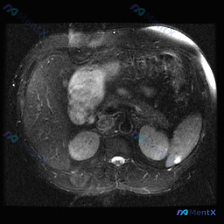

今天整理了一个挺有意思的影像读片病例,有点「答非所问」但非常考验临床思维,和大家分享一下思路。 --- 病例背景与影像资料 用户明确问的是「脾脏病变」,提供的是一张腹部MRI-T2加权轴位图像。 先直接说针对「脾脏」的第一判断: 👉 在这张图像上,脾脏实质信号均匀,皮髓质分界清晰,没有看到局灶性的高...

最近看到一个腹部MRI的病例,觉得在鉴别诊断上挺有代表性的,整理一下资料和思路跟大家分享。 先看影像资料(轴位T1序列) - 肝脏、胰腺、胆道、双肾及腹膜后:都没看到明显异常信号或占位,肝内血管、胆总管也不宽,腹膜后没见肿大淋巴结。 - 脾脏(重点):形态大致正常,但实质内有一个边界比较清楚的异常信...

看到一份很有意思的影像读片案例,用户的问题聚焦在“脾脏病变”,但影像本身却给了我们一个完全不同的方向,整理一下思路和大家分享。 --- 先看影像基本情况 - 序列:腹部MRI T2加权轴位像 - 用户焦点:脾脏病变 关键影像发现(按实际读片顺序) 1. 肝脏、胆囊、胰腺:未见明显异常信号或肿块,胆管...

整理了一份腹部MRI-T1加权轴位平扫的病例资料,同时结合了完整的分析思路,分享出来一起讨论。 核心影像表现 1. 脾脏:体积增大,内部可见多发明显的低信号结节影/斑片影,呈弥漫性分布,边界相对模糊 2. 肝脏:肝实质信号欠均匀,可见多发斑点状、类圆形低信号影散在分布 3. 右侧肾上腺区:可见类圆形...